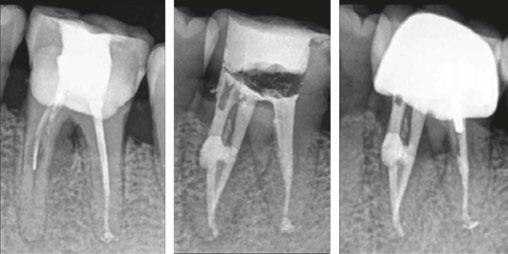

Regarding the obturation, the best results were observed with the use of thermoplasticized gutta-percha injection techniques.3,4,8,17-20 In this study, a thermofluid gutta-percha technique was used in 45 teeth, presenting adequate filling adaptation to the dentin walls in 43 of those cases. It is important to high-

light the studies by Ulusoy, et al.,21 who mention that the ex vivo use of System B™ and Obtura II in IRR fillings produced a temperature increase above the critical limit. In any case, these authors consider that the few seconds of thermal increase and the cooling action of the periodontium ligament in vivo would be a barrier to avoid thermal damage.

When the IRR communicates with the periodontium area, MTA, Biodentine® (Septodont USA) or similar product is the filling of choice,3,4 (Figures 5A, 5B, 5C).

Conclusions

The prevalence of IRR was higher in the upper incisors and lower molars, being located predominantly in the middle and apical thirds of the root canal. Its walls are generally regular and continuous. The use of thermoplasticized gutta-percha techniques allowed the adequate filling of the IRR cavities. Root canal treatment and retreatment provided adequate conditions to achieve a successful outcome.